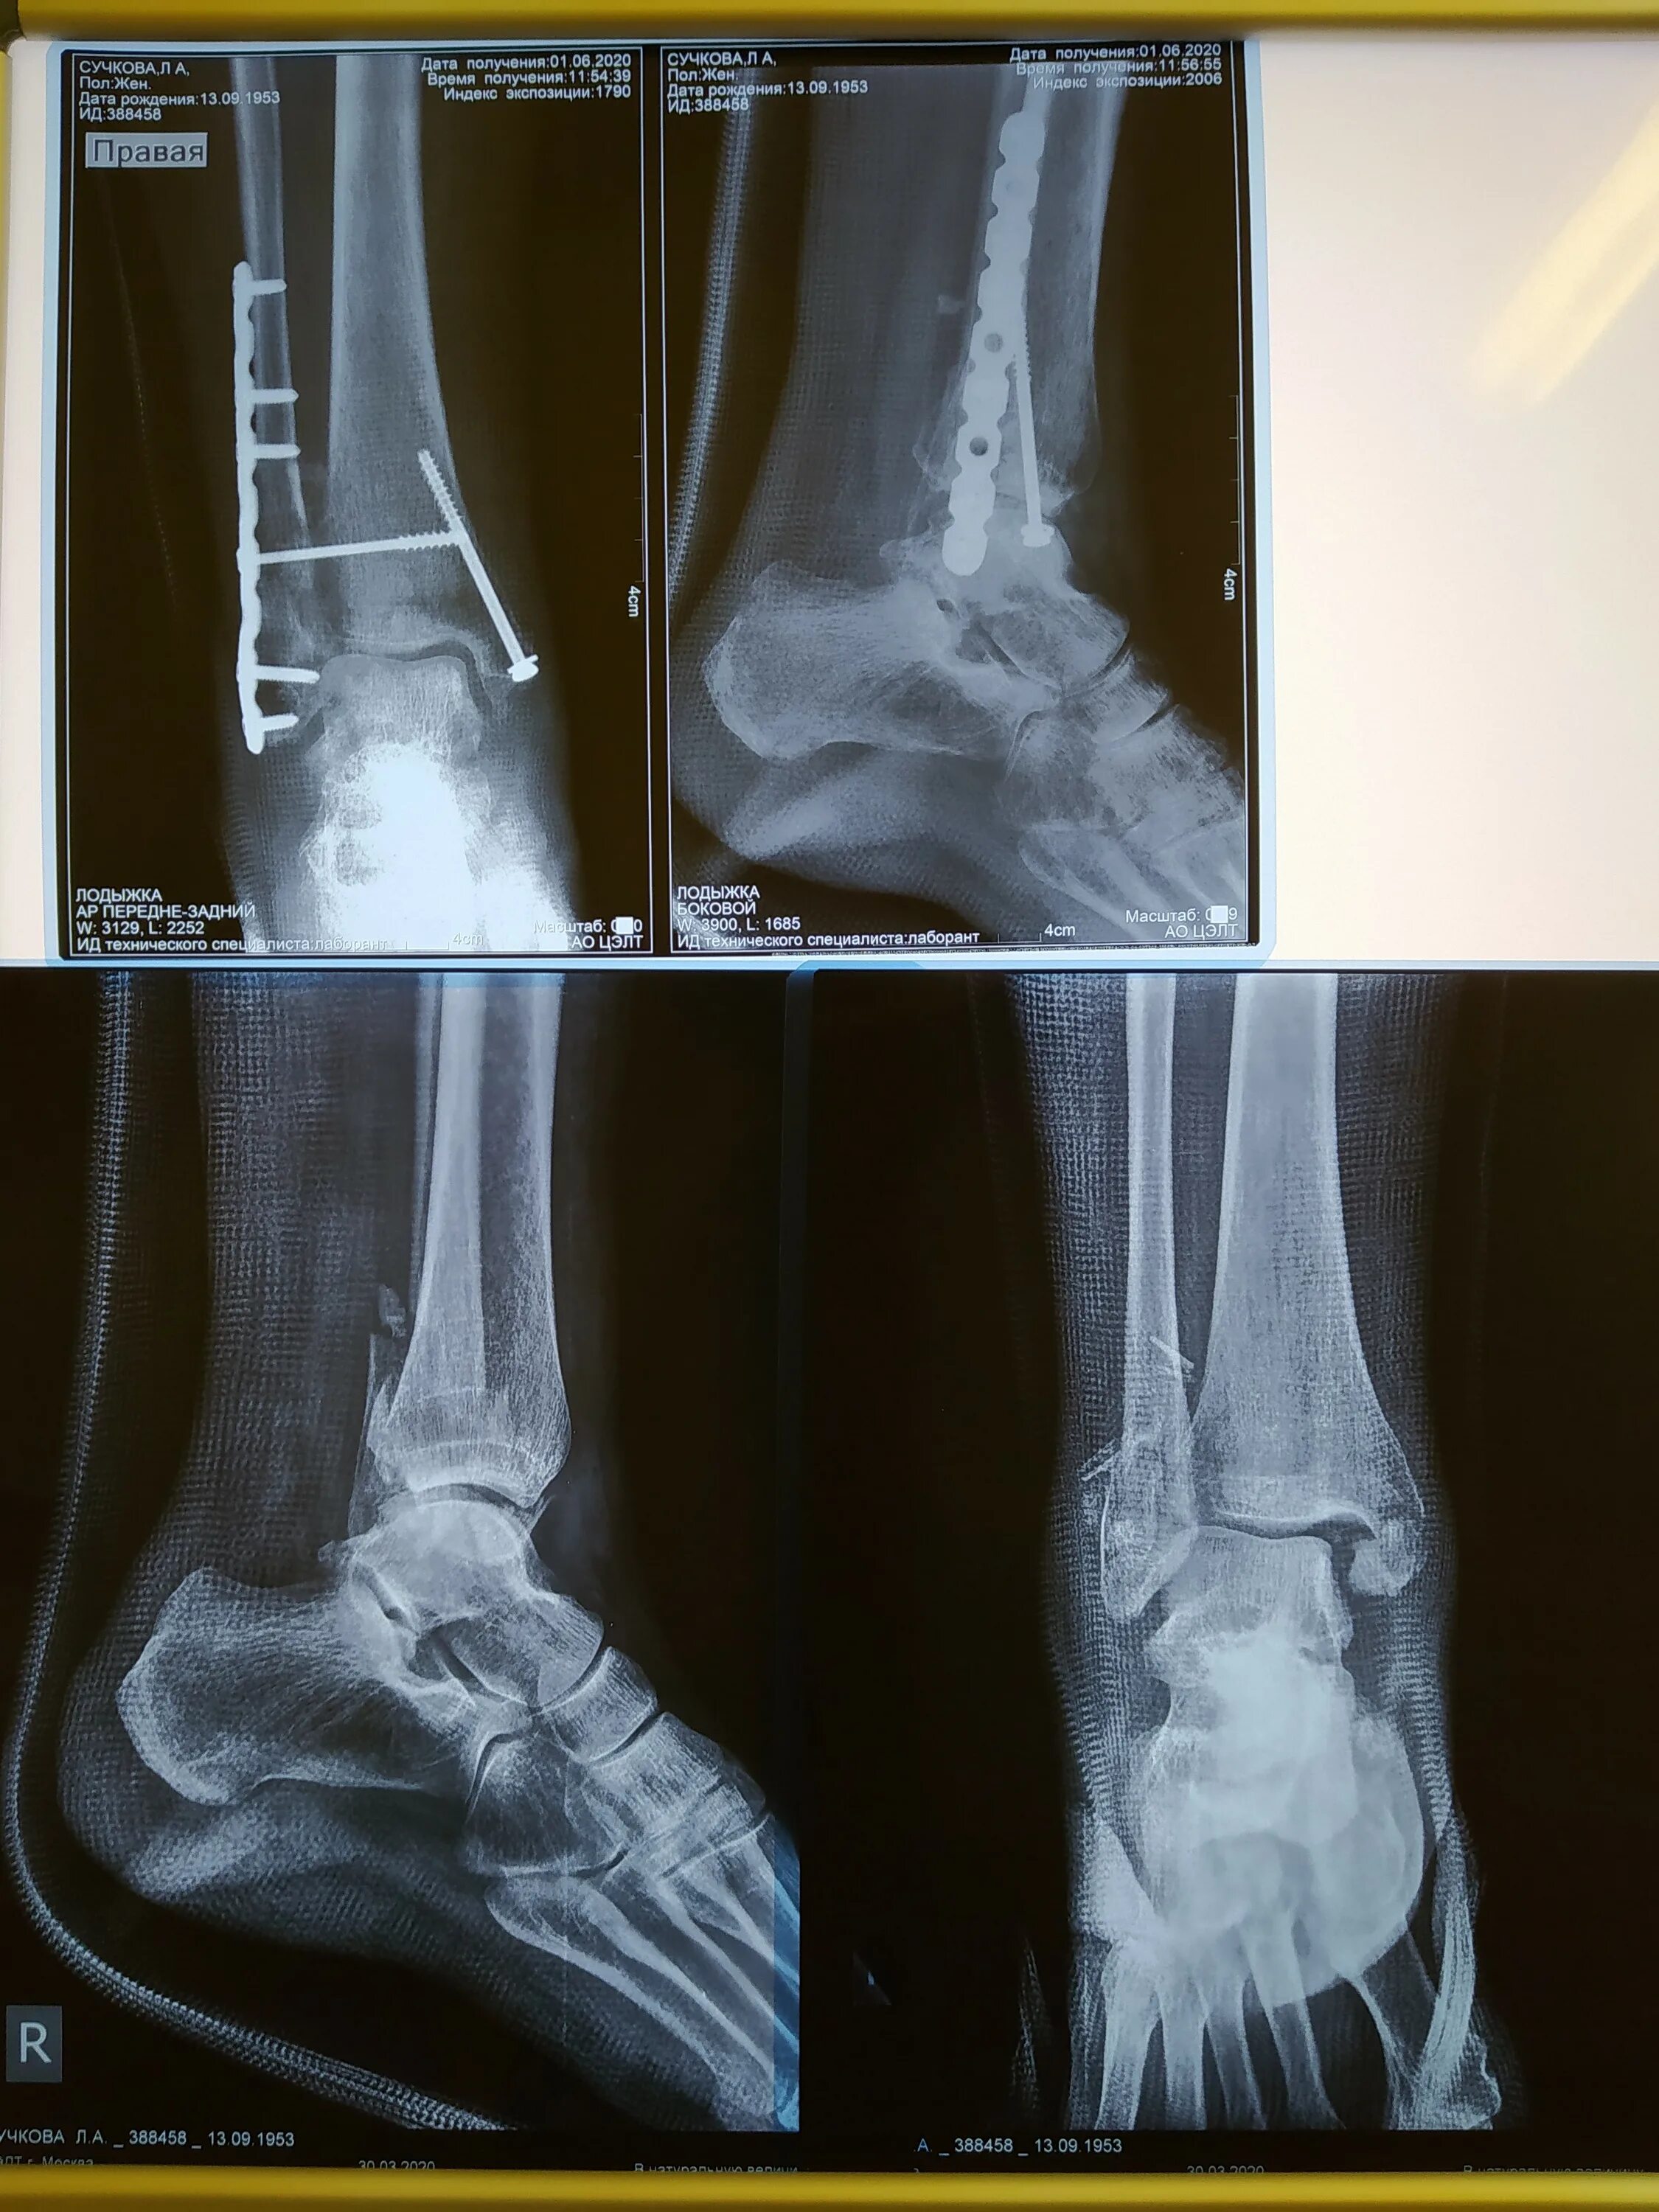

Через сколько срастается перелом лодыжки